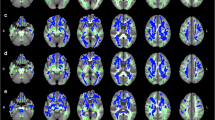

Each individual’s DWI images and b-vectors were registered to the I0 image using FSL’s FLIRT (mutual information metric) (Jenkinson et al. 2002) to correct for subject motion. Brain tissue was extracted with FSL’s Brain Extract Tool (Smith 2002). Tensors and fractional anisotropy (FA) values were reconstructed using linear least squares fitting. Whole brain tractography was obtained by streamline integration with trilinear interpolation of the DWI and linear least squares fitting of the diffusion tensor. Tracking was performed with the tensors’s principal eigenvector with the following parameters: one random seed per voxel, second-order Runge-Kutta integration, an angle threshold of 35 degrees, an FA threshold of 0.15, and a minimum-length threshold of 10 mm.

FA images were registered with the Johns Hopkins University (JHU) white matter atlas using affine registration and FSL FLIRT to examine anatomical features of specific tracts. Tracts including the CGC, CGH, IFOF, and UF were selected due to previously established associations with global cognition (Baek et al. 2013; Booth et al. 2013; Cremers et al. 2016). Each tract was modeled separately by hemisphere and streamlines were selected for inclusion in each bundle using the JHU atlas regions-of-interest. Fibers were included in the bundle if at least 80 % of the arc length was contained in the bundle mask, and streamlines were culled within 0.8 mm of an existing tract were used to reduce redundancy (Zhang et al. 2003). FBL was computed from the total length of the streamlines included in the bundle. Eight participants failed processing during tract-specific analysis and therefore were only included in the whole brain analysis. FBL was normalized by dividing by total intracranial volume (Correia et al. 2008).